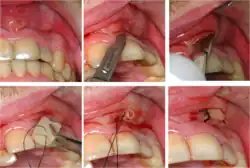

-

Pulp sensibility test using ethyl chloride (cold stimulus) -

Electric pulp tester -

Plastic wedge to identify pain on biting from a fractured tooth -

Transillumination demonstrating fracture -

Decay (green) with apical abscess (blue) -

Gutta-percha point indicating abscess origin